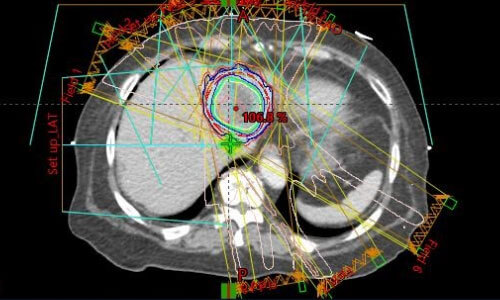

네 번째로, 치료계획을 최적화합니다. 얻어진 영상 정보를 기반으로 의료팀은 방사선의 최적 조사 각도, 선량, 그리고 치료 기간 등을 결정합니다. 고급 컴퓨터 소프트웨어를 활용하여 방사선이 암 조직에만 정확히 도달하도록 계획을 세우며, 건강한 조직에 미치는 영향을 최소화하기 위해 다양한 시뮬레이션을 수행합니다.